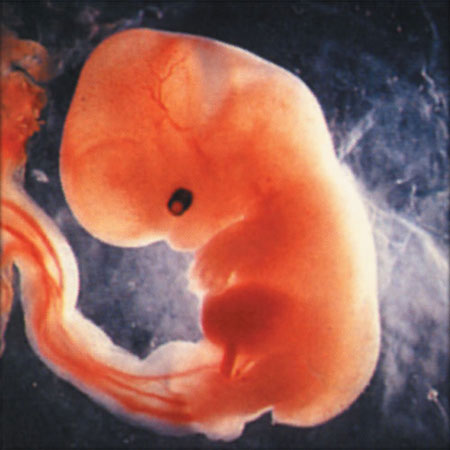

On Friday we headed uptown for our second ultrasound. Nobody told me that baby m0ves around in there at 12 weeks (thanks for the help, parenting books, keep up the good work!), so I just about freaked out when he arched his back and rubbed his face (or she/her, of course, we don’t find that out for another 6 weeks). Fortunately our tech was used to people gasping loudly. Sooooo cool.